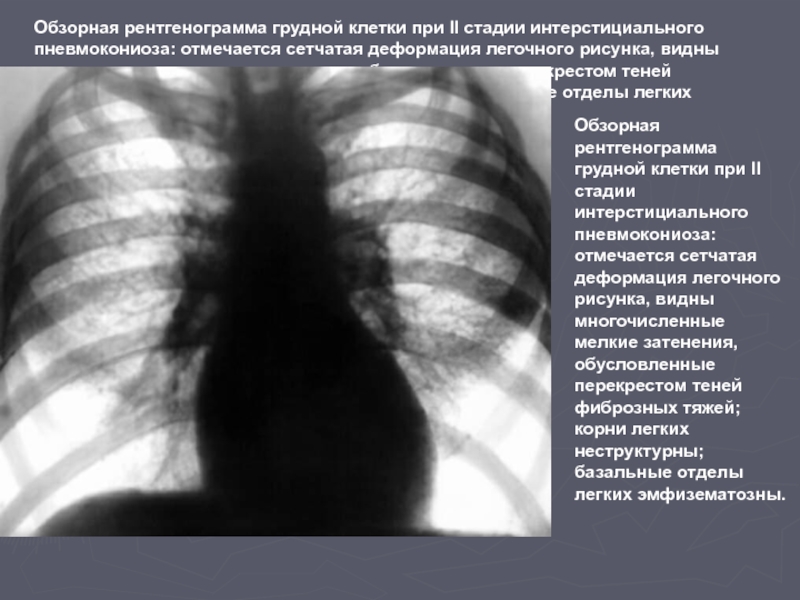

Фотографии, демонстрирующие обнаруженное усиление легочного рисунка

Раздел: Фотодневник открытий